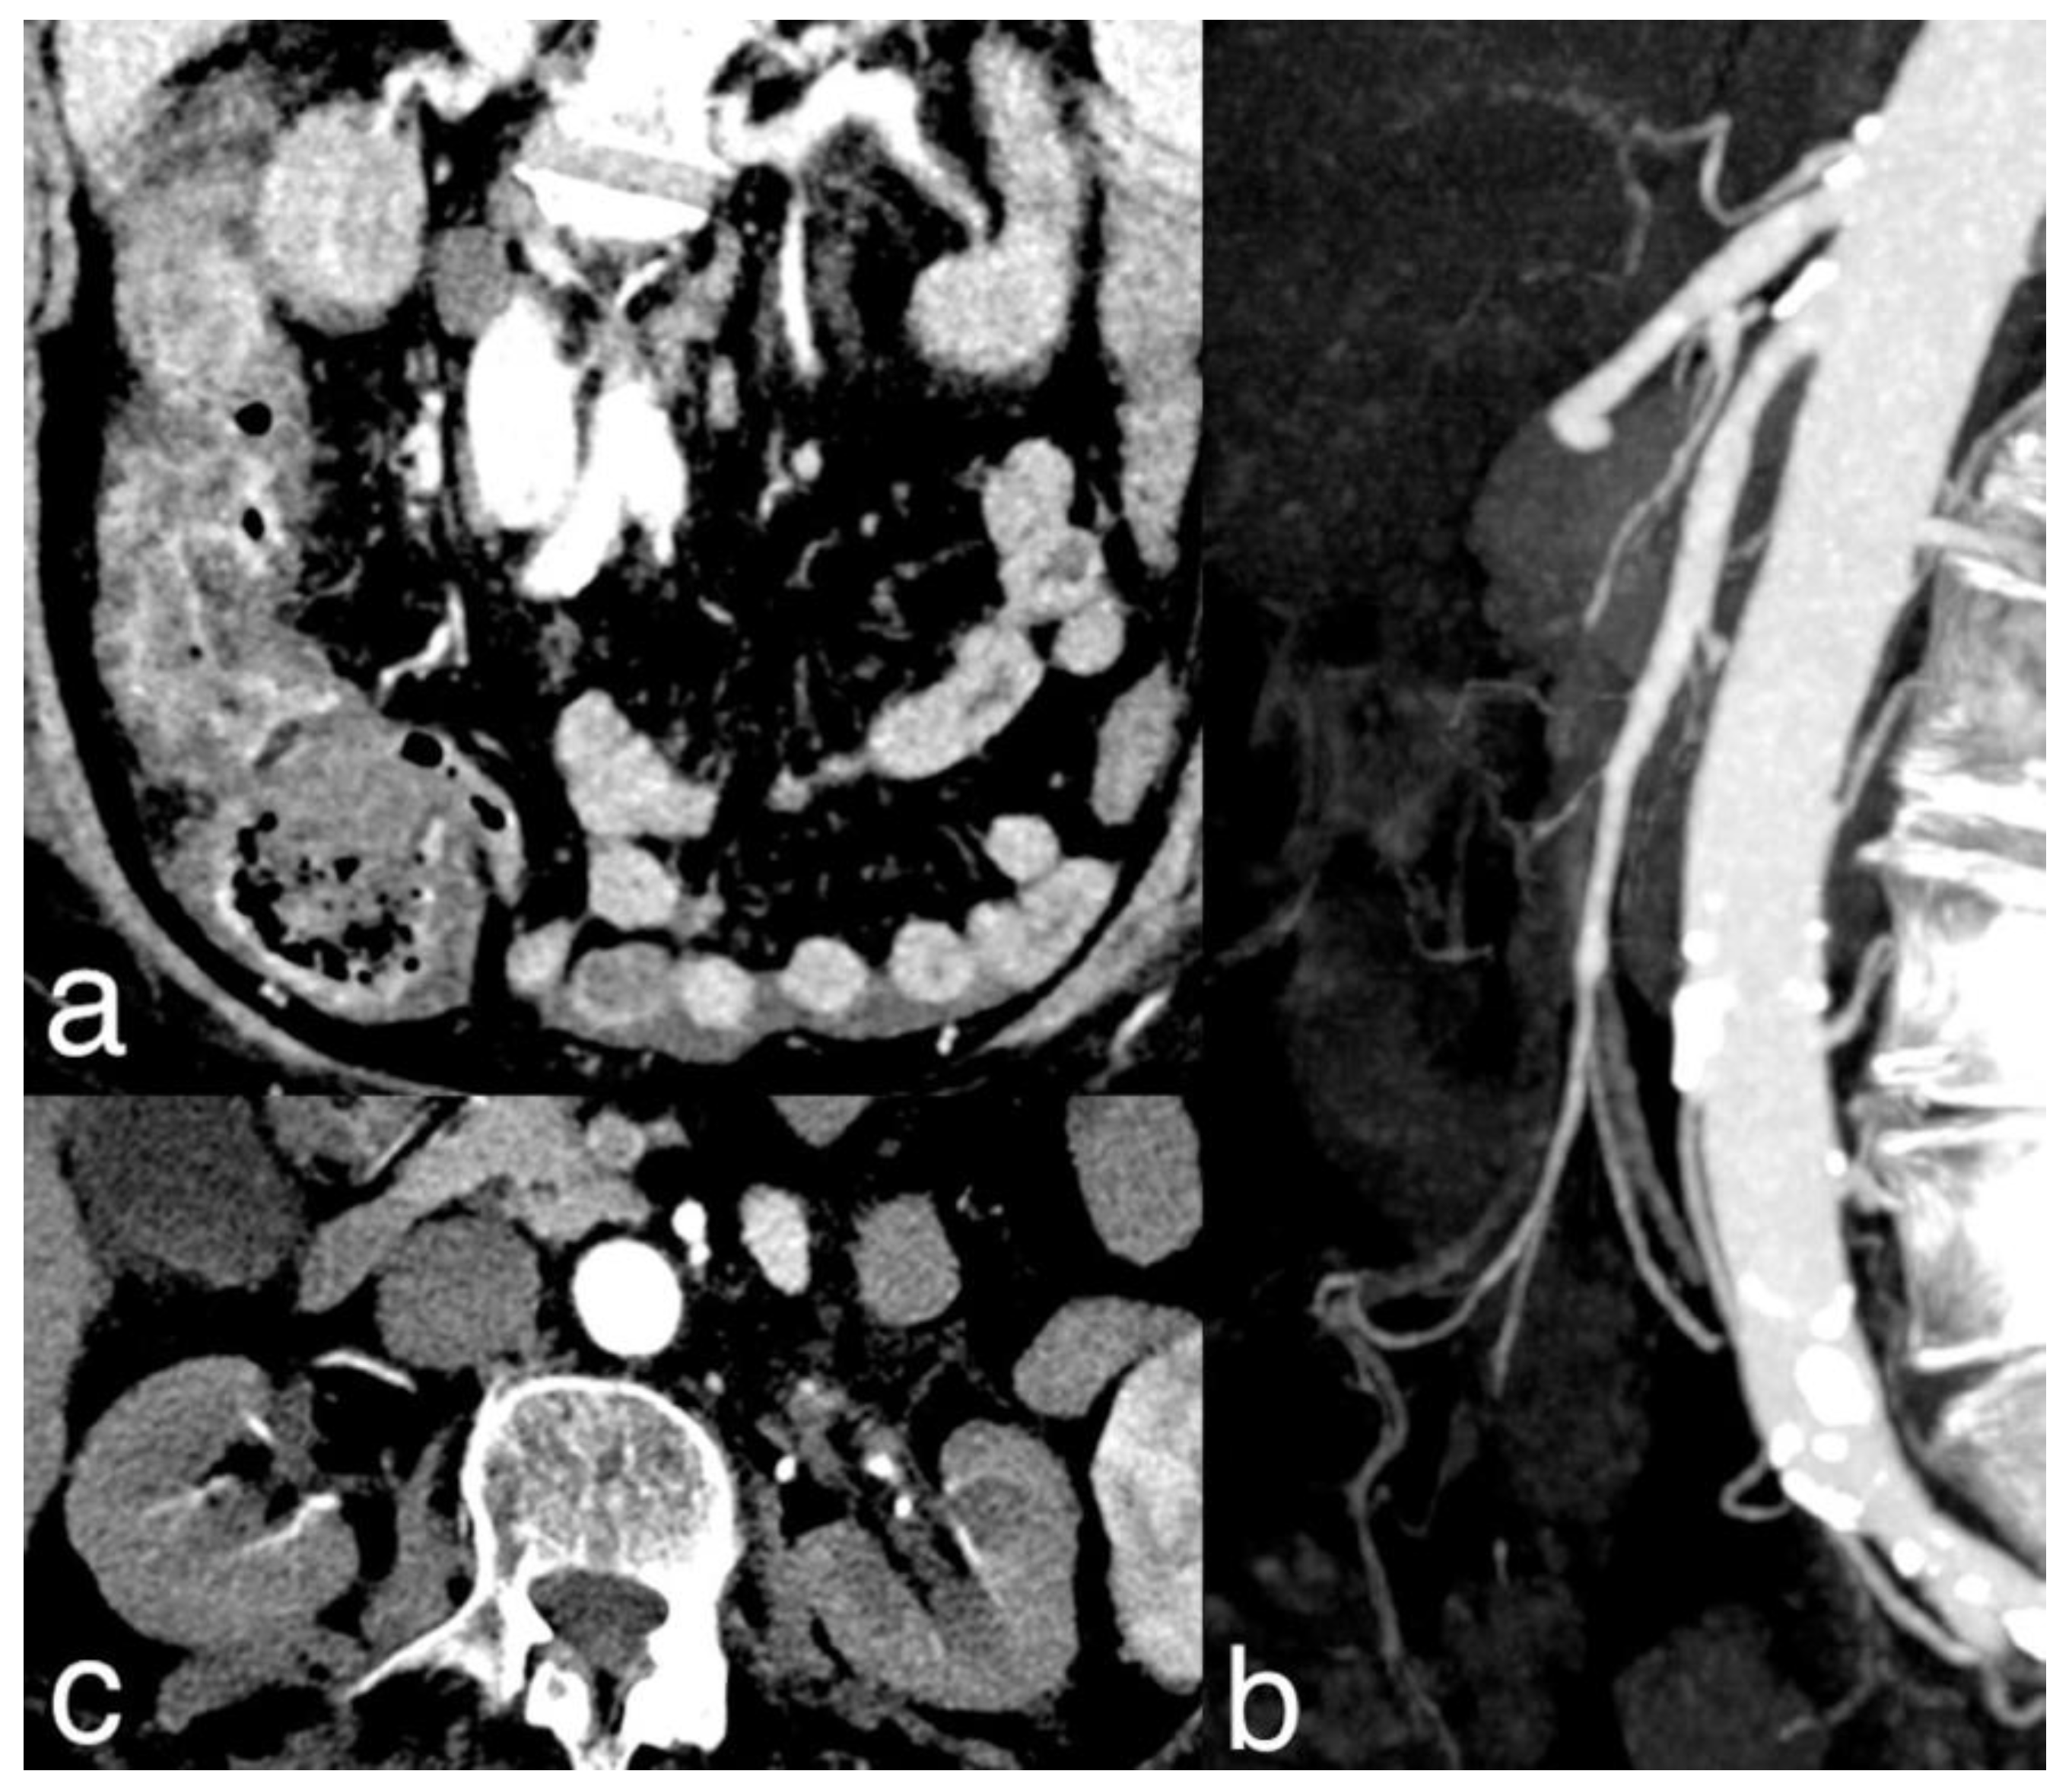

Figure 4. A 78-year-old woman with massive mesenteric ischemia. Atherosclerotic occlusion of the origin of the celiac trunk and the proximal SMA (figure 4a). Intrahepatic pneumatosis and gastrectasia (figure 4b). Hypoenhancing dilated paper-thin bowel wall, parietal pneumatosis and mesenteric venous pneumatosis (arrow) were reported (figure 4c). The patient died a few hours after emergency room access.